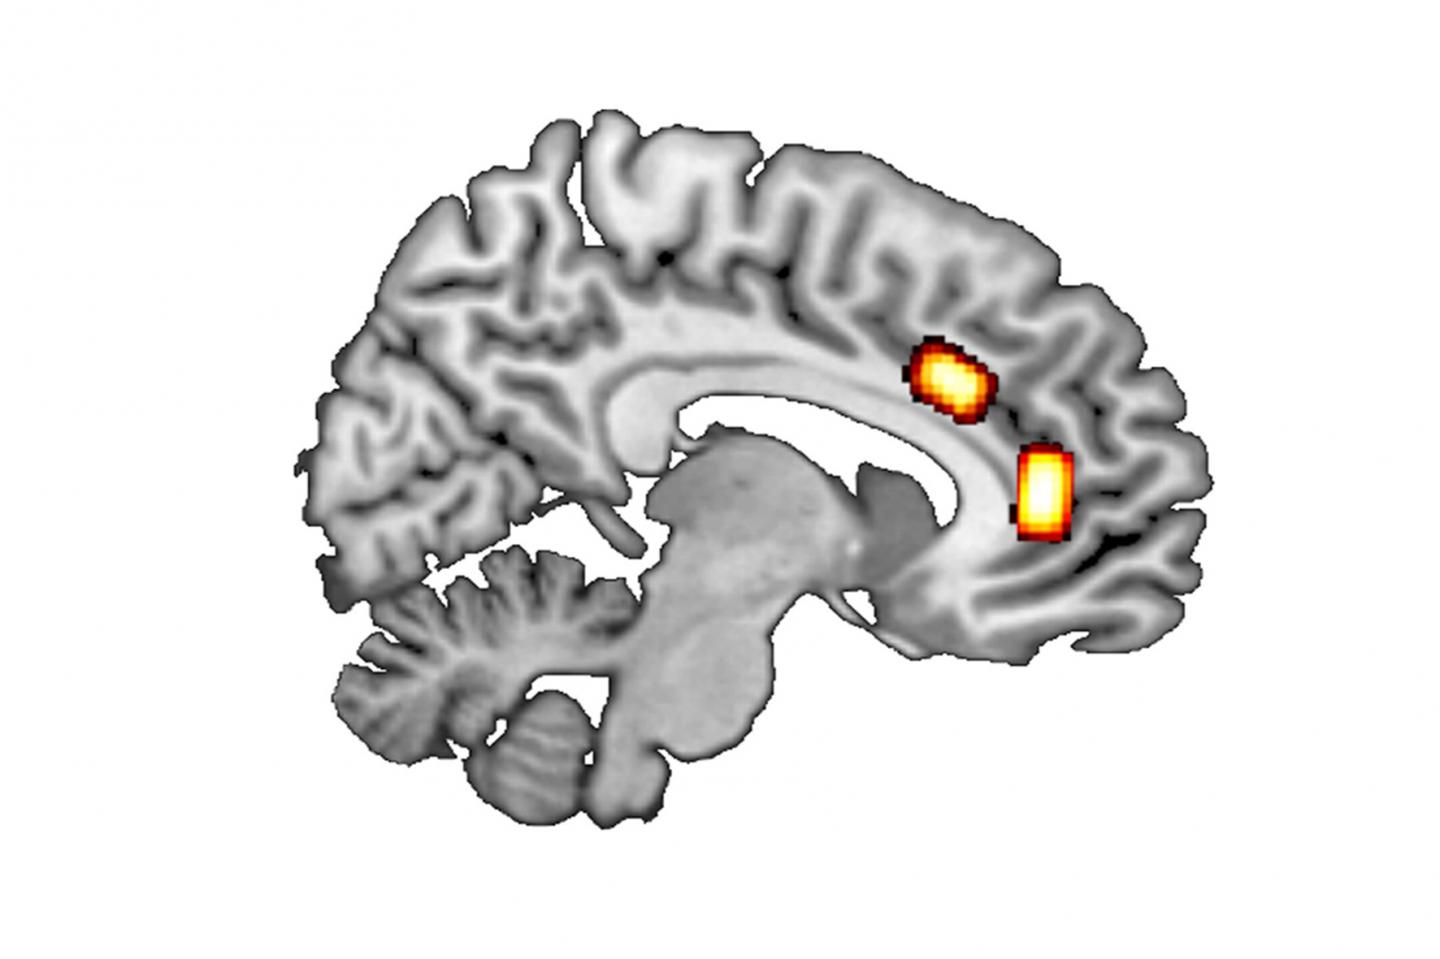

image: Longitudinal section of the brain: GABA/glutamate concentrations were measured at the locations marked (top: dorsal anterior cingulate cortex; further forward/bottom: ventromedial prefrontal cortex). view more

First, the researchers looked at so called ‘reward-based decisions’, which involve maximising reward by selecting the better of two options currently available. Luca Kaiser gives a simple example: “Where do I buy coffee on my way to work, depending on the price, quality and whether or not the café is on my way?” Previous results suggest that such decision-making processes in the brain are mainly processed in the ventromedial prefrontal cortex (vmPFC).

Unlike these reward-based decisions, ‘patch-leaving decisions’ are about long-term strategic considerations that include a careful balancing of immediate cost against (long-term) gain. An example of such a decision would be whether to move from Düsseldorf to Munich for a job offer. Prof. Jocham explains: “The job in Munich may offer a higher salary and a more interesting role, but may also involve stress and the effort involved in finding a place to live and moving to Munich – as well as higher rents and the loss of social contacts in Düsseldorf.” Thus, there are many factors that influence this type of decision. According to the literature, such decisions are made in the brain’s dorsal anterior cingulate cortex (dACC).

The two messenger substances glutamate and GABA may play a key role. The ratio between them, the so-called E/I balance, indexes the balance between excitatory and inhibitory neural transmission. The researchers used magnetic resonance spectroscopy to measure the concentrations of GABA and glutamate in different cortical areas of human volunteers.